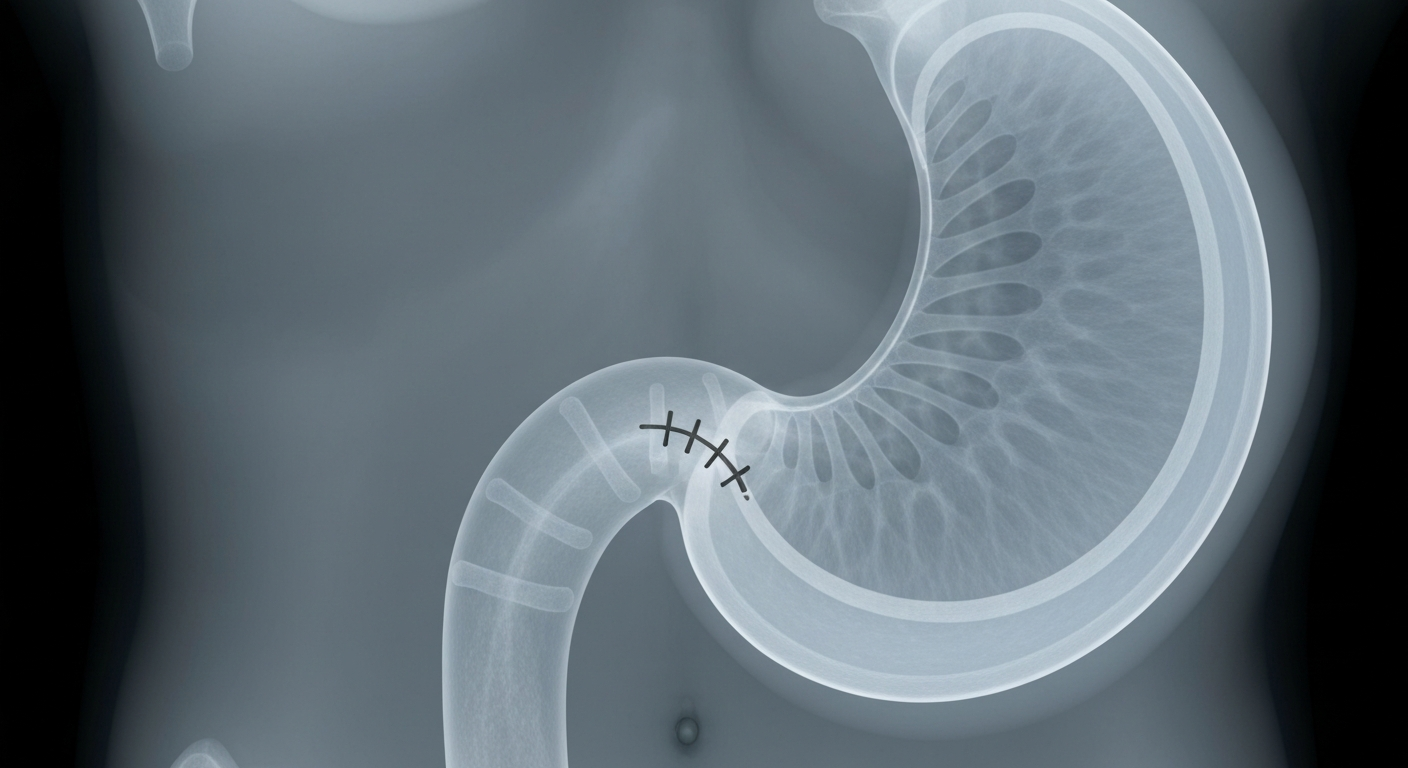

An endoscopic procedure helped this patient lose 60 pounds by limiting the size of her stomach.Today in OrlandoJayme Salerno, a 29-year-old New York resident, struggled with weight gain due to hypothyroidism and polycystic ovary syndrome (PCOS) for years. After trying various diets, medications, and workouts without success, Salerno opted for an endoscopic sleeve gastroplasty (ESG) procedure performed by Dr. Andre Teixeira at Orlando Health. The less-invasive ESG, which involves sewing part of the stomach closed to limit food intake, helped Salerno lose 60 pounds over 10 months, exceeding the typical weight loss for the procedure.

Salerno, who peaked at 225 pounds with a 36 BMI, tried numerous diets, workout regimens, and medications like GLP-1 and metformin, but nothing led to sustained weight loss. She eventually decided to pursue a medical procedure and spoke with Dr. Teixeira about options, including the less-invasive ESG. Salerno chose ESG because it would not require cutting into her body, and she felt comfortable with Dr. Teixeira's approach. After the 45-minute procedure, Salerno followed a liquid diet for 21 days and slowly reintroduced regular foods, while also committing to a strict exercise regimen. The weight loss was rapid, with Salerno shedding 60 pounds in 10 months, exceeding typical ESG results.